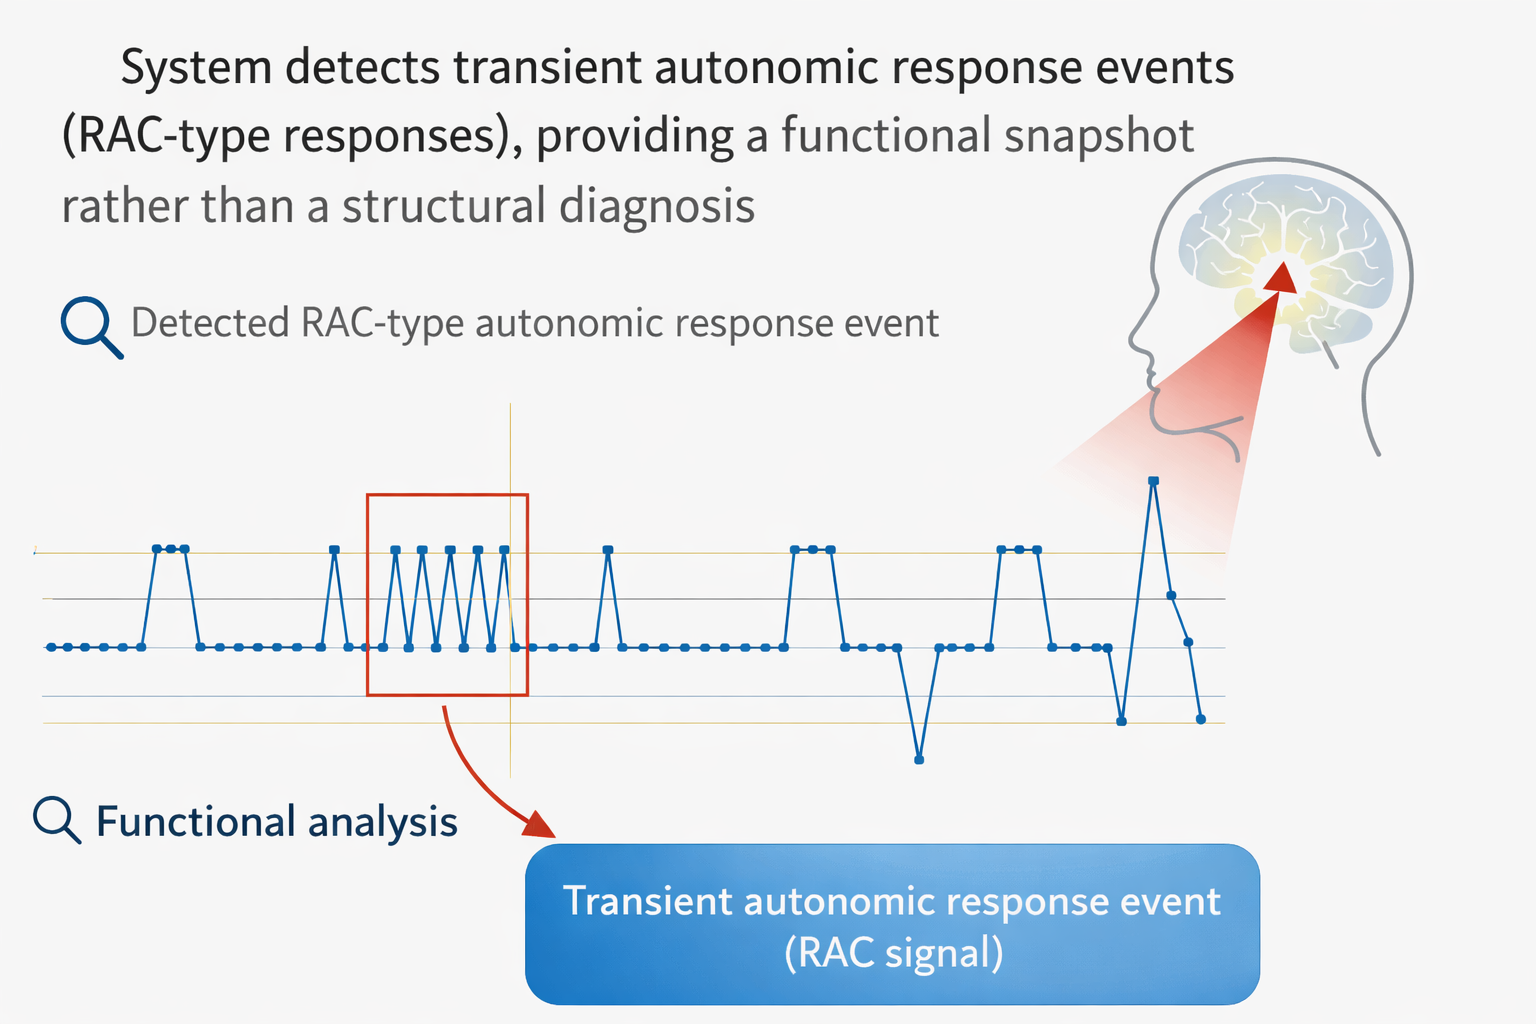

The DAMNIT-V Screen records transient autonomic response events (RAC-type responses) during exposure to defined test domains.

RAC Event Count

Results are expressed as the number of Reflex Auriculo-Cardiac (RAC) responses detected during a standardised 5-second exposure period.

A RAC event is a reproducible transient autonomic response pattern detected by the system.